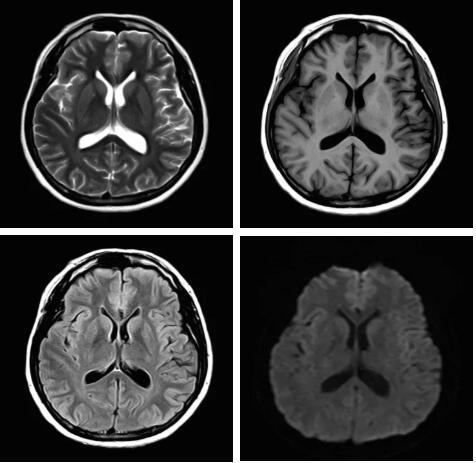

圖:Pure射頻成像鏈的優(yōu)化和改進使信噪比提升

3.Pure射頻成像鏈

從成像源頭的磁體采用鍍膜新磁體高密度薄層鍍膜貼合技術,獲得更好的磁場均勻度,奠定磁共振成像基礎;采用3D RSCE微雕梯度精準控制頻率和相位,輸出理想波形,實現渦流的“0”殘余,還原最真實的圖像信息;射頻接收端通過計算機人工智能對信號抗干擾處理,把信號放大并去除梯度、磁場等對信號干擾,再經過二次人工智能信號識別,去除噪聲污染獲得純凈的信號;通過Pure射頻成像鏈的優(yōu)化和改進使信噪比提升40%,這是磁共振領域革命性的顛覆和改變。